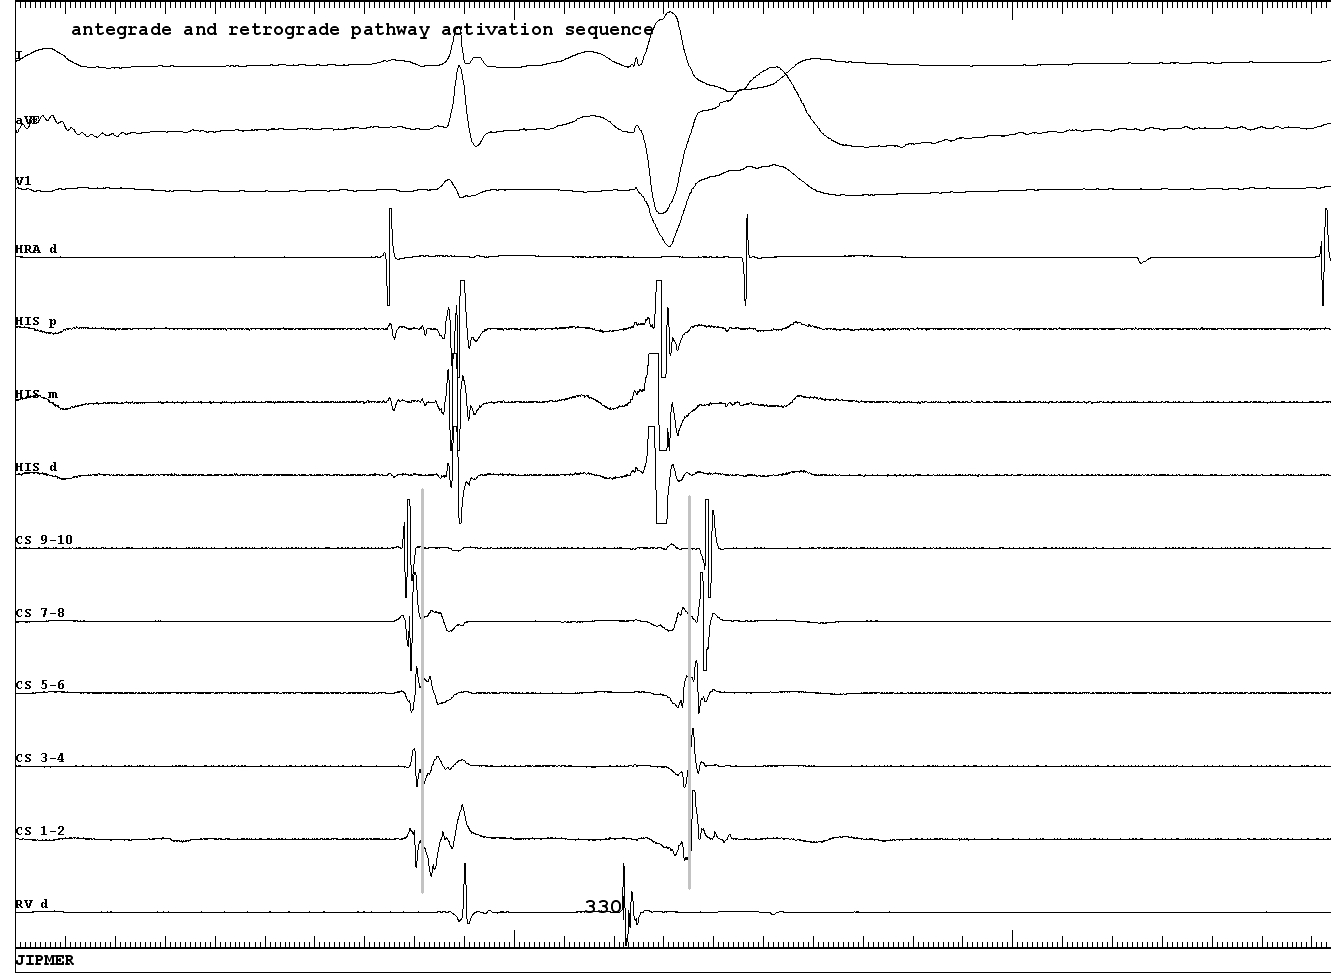

antegrade_ap_potential.png

Jackman WM, Friday KJ, Yeung-Lai-Wah JA, Fitzgerald DM, Beck B, Bowman AJ, Stelzer P, Harrison L, Lazzara R. New catheter technique for recording left free-wall accessory atrioventricular pathway activation. Identification of pathway fiber orientation. Circulation. 1988 Sep;78(3):598-611. doi: 10.1161/01.cir.78.3.598.

retrograde_ap_potential.png